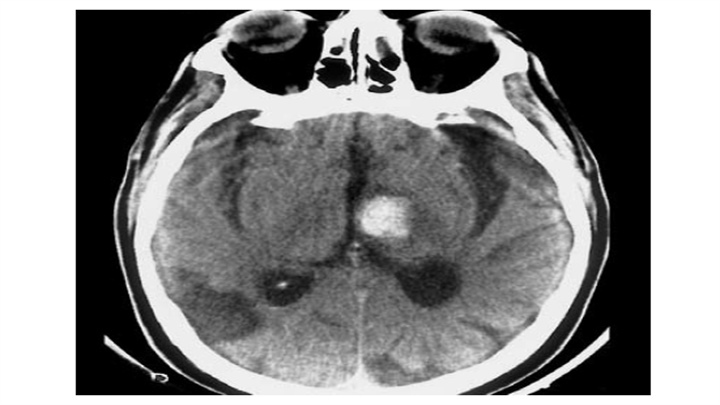

左侧小脑半球血肿。第四脑室变形、移位。